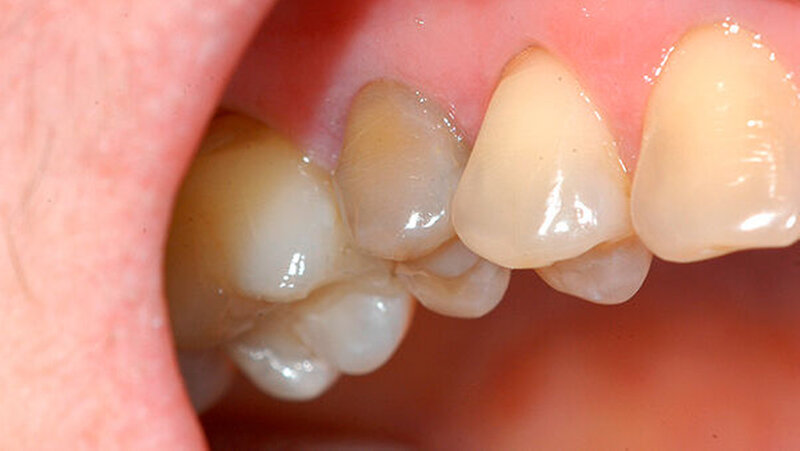

Nachdem die Patientin darüber aufgeklärt wurde, wie der Zahn möglicherweise erhalten werden kann, wurden die Zahnfragmente nach Gabe einer Infiltrationsanästhesie schonend extrahiert (Abbildung 3). Nach der Extraktion wurden die zwei Zahnfragmente zunächst in der Zellnährlösung einer Zahnrettungsbox (Medice Pharma, Iserlohn) geschwenkt, um sie von Blut und Gewebe zu säubern. Das apikale Granulationsgewebe, das bei der Extraktion an der Wurzelspitze verblieben war, konnte manuell mit einer Luer Zange entfernt werden.

Danach wurden die Wurzelkanalwände des jeweiligen Fragments mit einem diamantierten torpedoförmigen Schleifkörper präpariert, wobei die Frakturflächen nicht berührt wurden (Abbildung 4). Auf die beiden Frakturflächen sowie die Wurzelkanalwände wurde anschließend ein selbstätzender All-In-One Dentinhaftvermittler (Optibond All-In-One; Kerr, Orange, USA) appliziert und die zwei Fragmente mithilfe eines dualhärtenden Komposits (Nexus NX 3; Kerr) adhäsiv zusammengesetzt (Abbildung 5).

Dabei wurde strikt darauf geachtet, dass weder Überschüsse des Dentinhaftvermittlers noch des Komposits auf die Wurzeloberfläche gelangten. Anschließend wurden die apikalen 3 mm der Wurzelspitze im Sinne einer Wurzelspitzenresektion entfernt. Die Resektionsfläche wurde mit einem feinen diamantierten zylinderförmigen Schleifkörper von retrograd etwa 2 mm in den Wurzelkanal hinein präpariert und die Frakturlinie mit einer Flamme dezent erweitert (Abbildung 6).